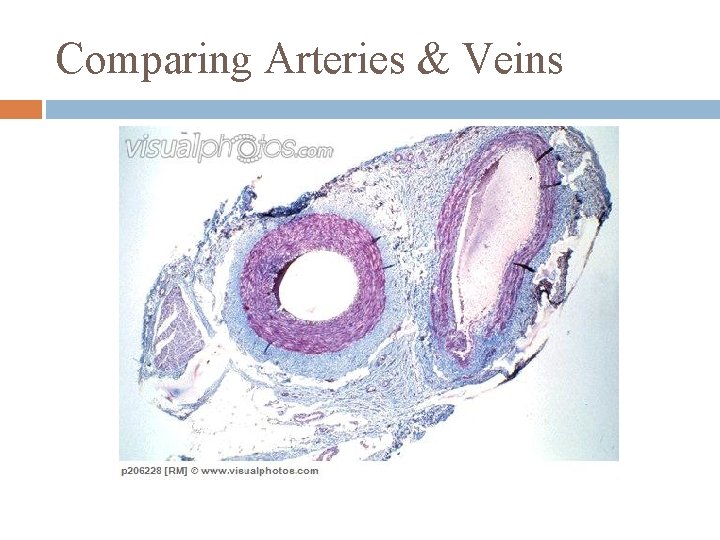

Arteries any blood vessel carrying blood away from heart designed to withstand higher pressure than veins elastic: must swell to take up blood expelled by the heart swelling stretches elastic tissue & keeps the blood pressure fairly high between heart beats small arteries (arterioles)have muscles that control their diameters (precapillary sphincters): used to control blood flow thru an organ

cross-section of artery

Veins any blood vessel with blood flowing toward the heart low pressure vessels can expand to accommodate differing volumes of blood flow contain valves to stop backflow of blood

cross-section of vein with valve

Comparing Arteries & Veins